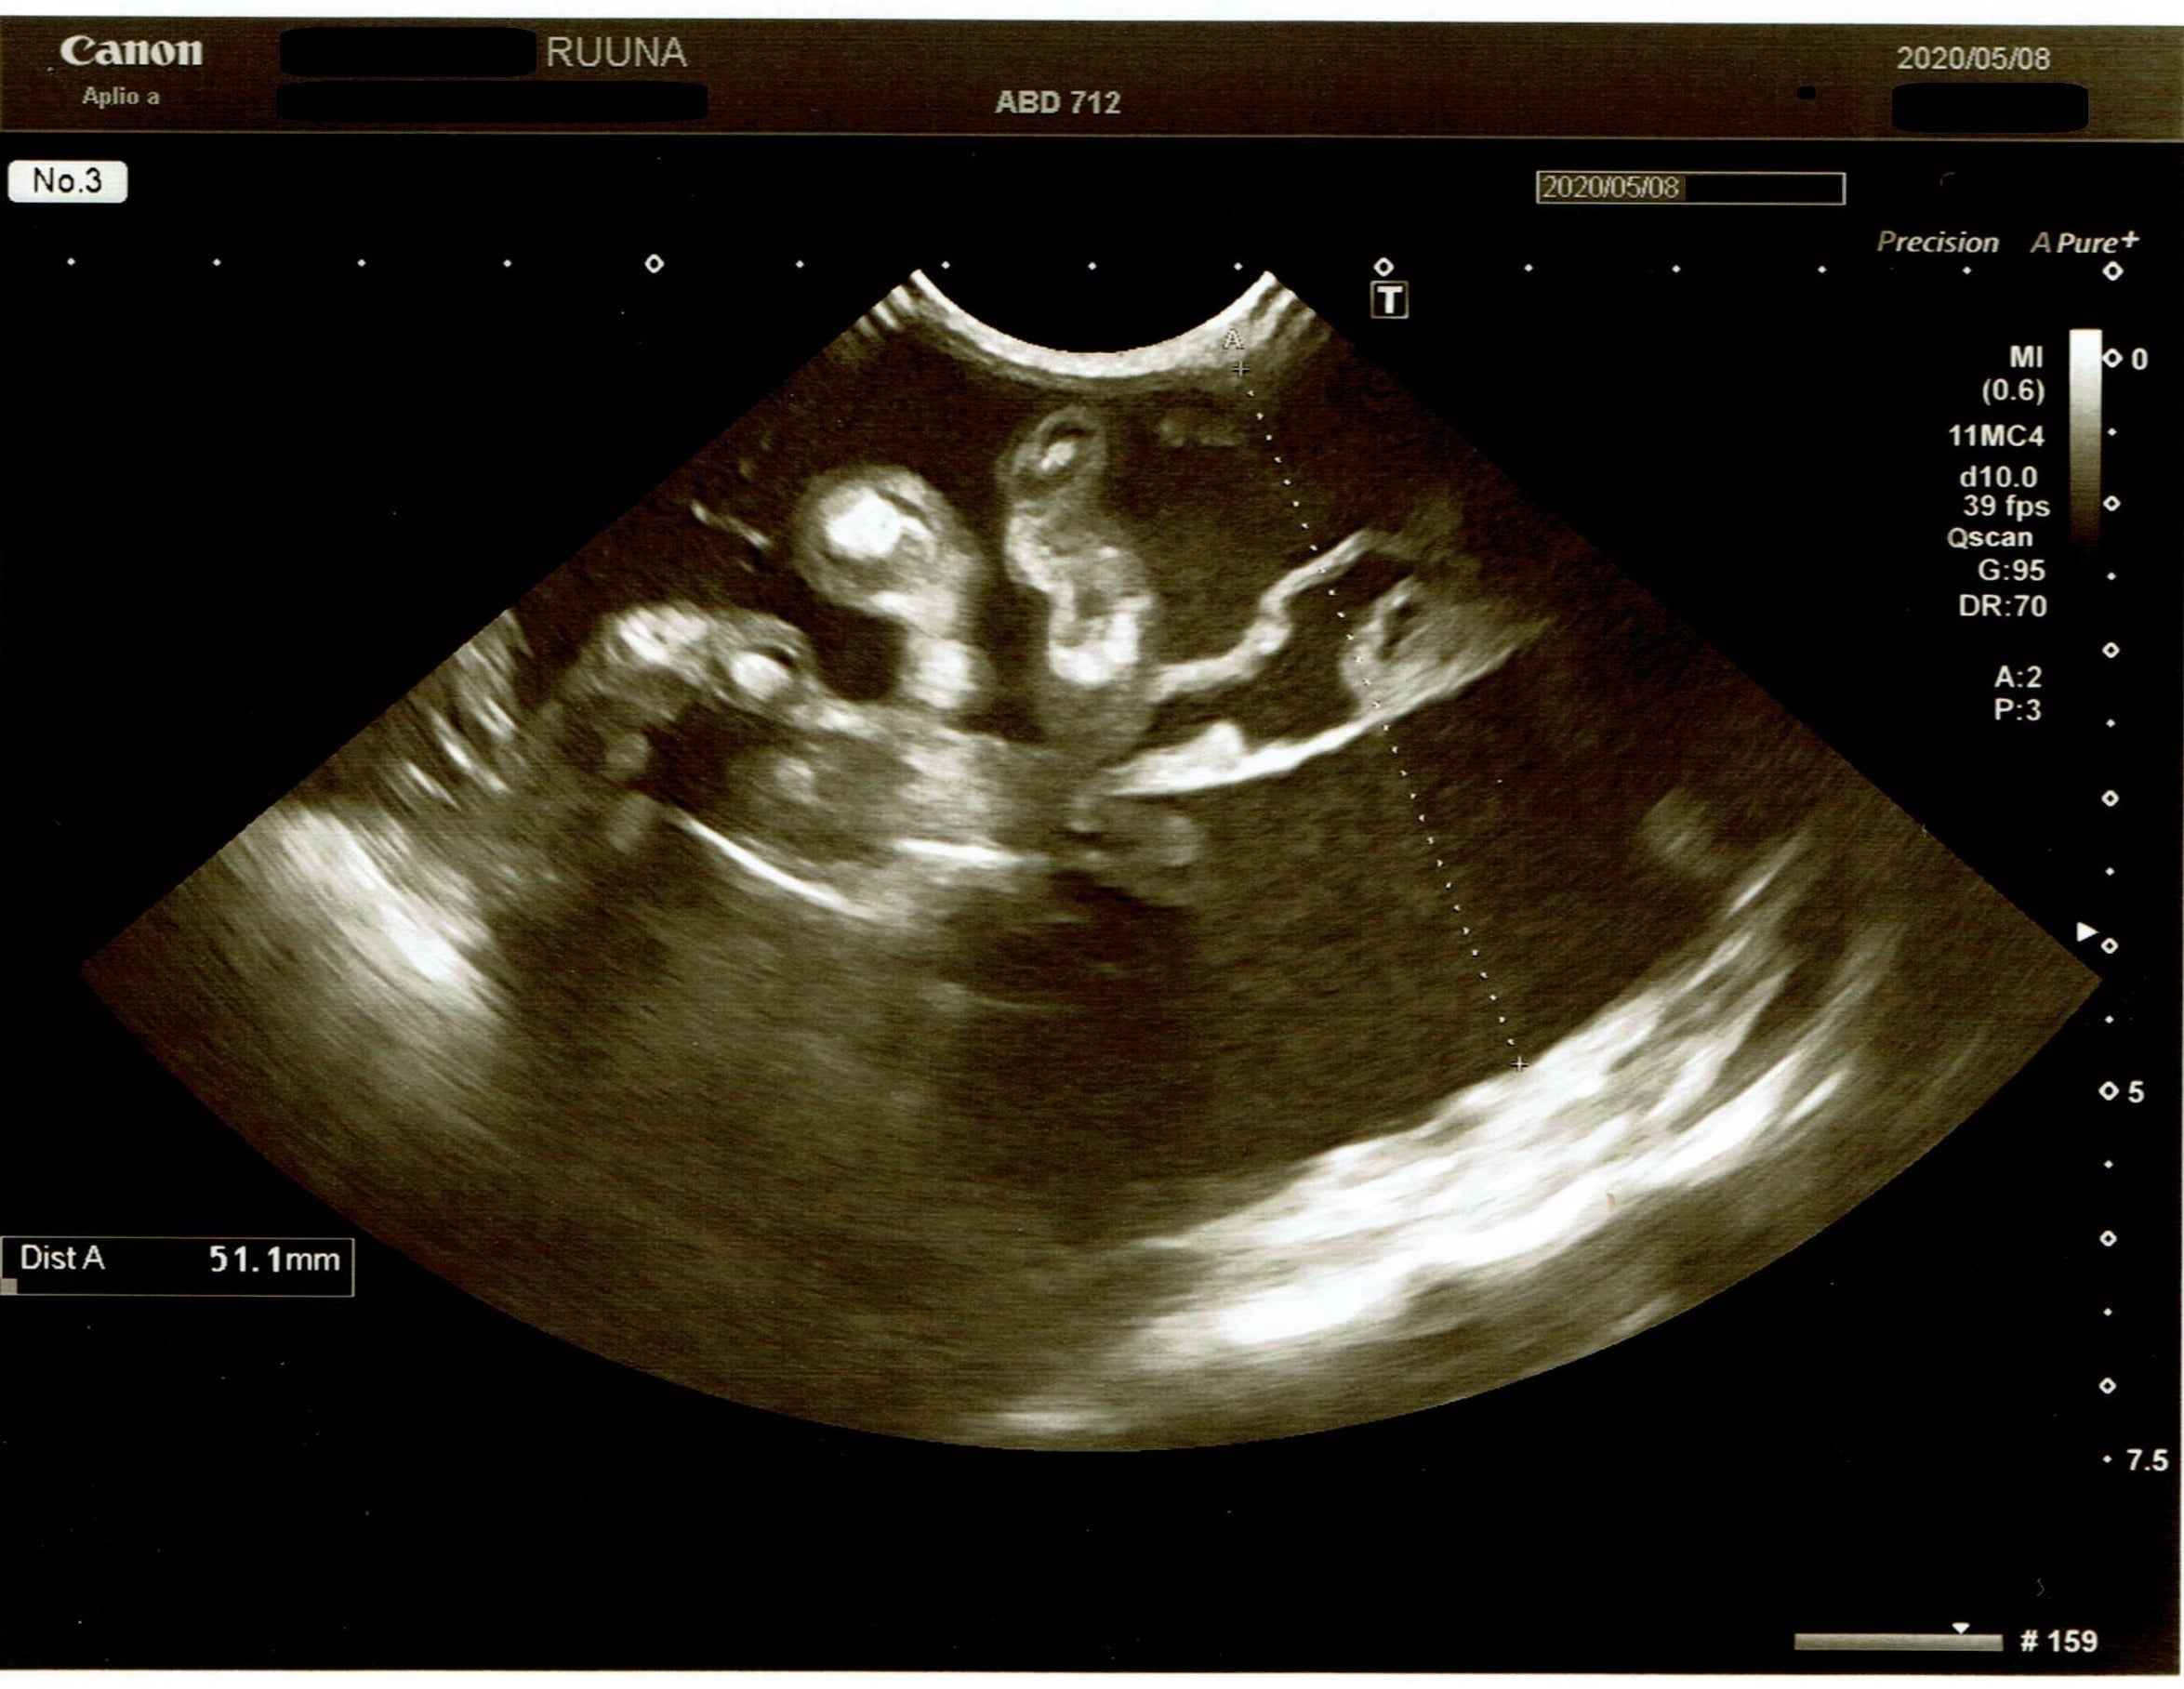

5月8日

FIP治療ができるB動物病院に相談しに行き、さらに精密検査をしました。

↑

黄疸あり。炎症データ高値。貧血はギリギリセーフ。肝機能は問題なし。

炎症マーカー高値

5㎝の腹水貯留あり

腹水が1週間ちょっとで3〜4㎝増え、増悪していました。

血液中に猫コロナウイルスなし

ルゥナの症状は、腹水と食事摂取量が一日分の半分。

精密検査の結果、「FIP(ウェットタイプ)の初期」と診断されました。